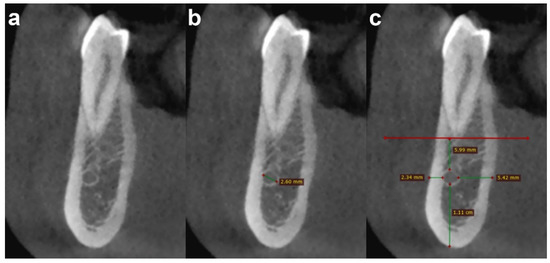

All MIC parameters were evaluated on cross-sectional images at four anatomical reference levels (first premolar, canine, lateral incisor, and central incisor) by two observers (A.B. and D.D.S., with 10 and 2 years of experience in dental CBCT, respectively) (Figure 3). The two observers performed the image analysis in a consensus reading (i.e., performed together, not independently). We used this method of analysis to simulate a surgical planning situation (i.e., a preoperative imaging assessment by a surgical team).

Figure 3.

Cross-sectional CBCT images show an example of the steps of image analysis of the MIC at the first premolar level, as follows: (a) detection; (b) diameter measurement; and (c) distance measurement from adjacent anatomical landmarks (cortical plates and first premolar apex).